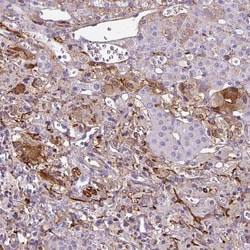

Invitrogen™ NGB Polyclonal Antibody

Immunogen sequence: ESLLYMLEKC LGPAFTPATR AAWSQLYGAV VQAMSRGWDG E Highest antigen sequence identity to the following orthologs: Mouse - 93%, Rat - 95%.

| Immunohistochemistry (Paraffin) | |

| Recombinant protein corresponding to Human NGB. Recombinant protein control fragment (Product #RP-104263). | |